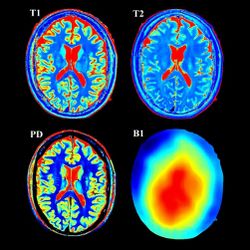

Магнитно-резонансный томограф работает на основе магнитного поля и радиоизлучения. МРТ-диагностика ценится за высокое качество визуализации и отсутствие вредного влияния на организм пациента. Аппарат МРТ обеспечивает сканирование сосудов, тканей и органов в необходимой плоскости по срезам толщиной от 1 мм.

Главная характеристика магнитно-резонансного оборудования – это мощность магнитного поля. Она определяет качество разрешения изображений и цену томографа. Всего есть три класса аппаратов: низко-, средне- и высокопольные.

Для большинства медучреждений вполне достаточно купить аппарат МРТ мощностью 1,5 Тесла. Он обеспечит экспертный класс диагностики с достаточной помехоустойчивостью. Обследование с высокопольным томографом проходит значительно быстрее, но стоит дороже.